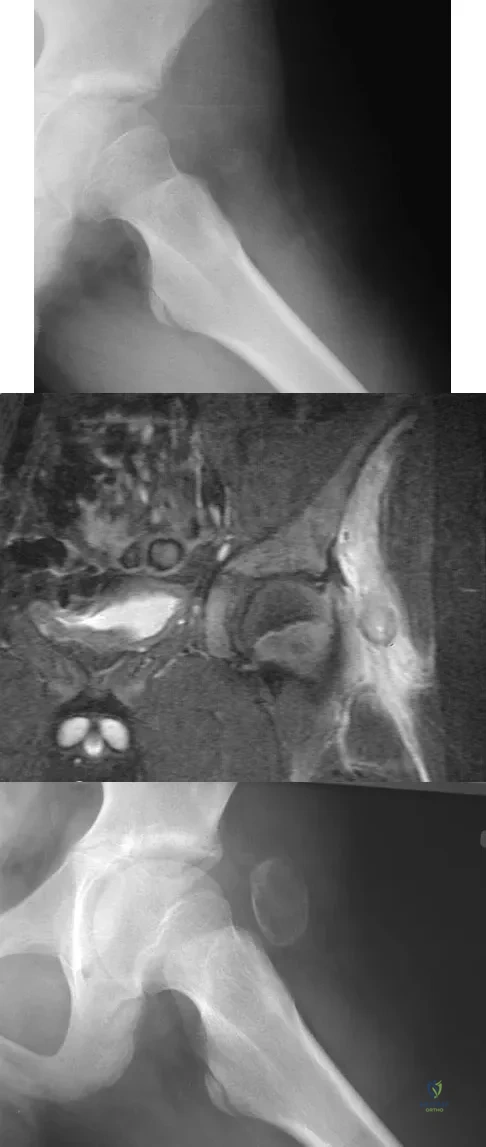

A 13-year-old boy has a painless "knot" over his left hip. History reveals that he injured his left hip playing soccer 4 months ago. A radiograph and MRI scan obtained at the time of injury are shown in Figures 7a and 7b. He is very active and is currently asymptomatic. A current radiograph is shown in Figure 7c. What is the next most appropriate step in management?

Explanation